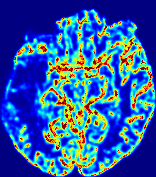

LesionRefer to captionRefer to captionRefer to captionRefer to captionRefer to captionRefer to caption𝐕rgbsubscript𝐕𝑟𝑔𝑏{\bf{V}}_{rgb}Refer to captionRefer to captionRefer to captionRefer to captionRefer to captionRefer to caption𝐕2subscriptnorm𝐕2{\|\bf{V}}\|_{2}Refer to captionRefer to captionRefer to captionRefer to captionRefer to captionRefer to captionRefer to caption3.53.53.52.82.82.82.12.12.11.41.41.40.70.70.70.00.00.0(mm/s)𝑚𝑚𝑠(mm/s)D𝐷DRefer to captionRefer to captionRefer to captionRefer to captionRefer to captionRefer to captionRefer to caption0.0200.0200.0200.0160.0160.0160.0120.0120.0120.0080.0080.0080.0040.0040.0040.0000.0000.000(mm2/s)𝑚superscript𝑚2𝑠(mm^{2}/s)Slice #1Slice #2Slice #3Slice #4Slice #5Slice #6

Figure 3: PIANO feature maps for one stroke patient, where the lesion is located in the left hemisphere. Top row: segmented stroke lesion region (white) on different slices, obtained from ISLES 2017. The corresponding slices for the PIANO feature maps are shown in the following rows.

For a better insight into an estimated velocity field 𝐕𝐕{\bf{V}} and diffusion field 𝐃𝐃{\bf{D}}, we compute the following maps: (1) 𝐕rgbsubscript𝐕𝑟𝑔𝑏{\bf{V}}_{rgb}: Color-coded orientation map of 𝐕=(Vx,Vy,Vz)T𝐕superscriptsuperscript𝑉𝑥superscript𝑉𝑦superscript𝑉𝑧𝑇{\bf{V}}=(V^{x},V^{y},V^{z})^{T}, obtained by normalizing 𝐕𝐕{\bf{V}} to unit length and mapping its 3 components to red, green, blue respectively; (2) 𝐕2subscriptnorm𝐕2\|{\bf{V}}\|_{2}: 222 norm of 𝐕𝐕{\bf{V}}; (3) D𝐷D: scalar field in Eq. 5.

Fig. 3 and Fig. 4 show the PIANO feature maps estimated from two ISLES 2017 patients: all are highly consistent with the lesion in both cases. Details of the blood flow trajectories are revealed in 𝐕rgbsubscript𝐕𝑟𝑔𝑏{\bf{V}}_{rgb} by the ridged patterns and the sharp changes of colors in the unaffected (right) hemisphere, while the flat patterns appearing within the lesion provide little directional information about the velocity and indicate low velocity magnitudes. Velocity magnitudes are more directly visualized via 𝐕2subscriptnorm𝐕2\|{\bf{V}}\|_{2}, from which one can easily locate the lesion where 𝐕2subscriptnorm𝐕2\|{\bf{V}}\|_{2} is low. D𝐷D also indicates lower diffusion values in the lesion, though with less contrast potentially due to the fact that it captures the accumulated effect of CA diffusion at the voxel-level.